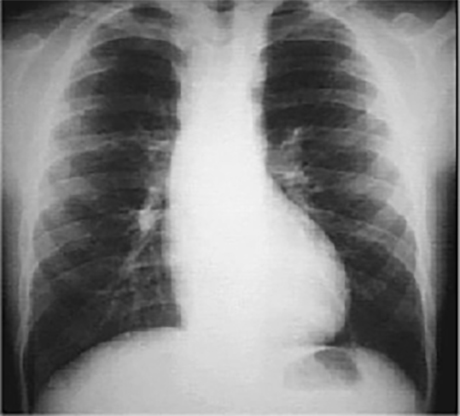

This chest X ray shows rib notching.

In this PA view, it is demonstrated by a

scalloped or notched appearance of the inferior rib margin, especially well seen in the posterior fourth to seventh ribs.

This is typically seen in patients with coarctation of the aorta, where collateral circulation in the intercostal arteries causes them to become large and tortuous and erode the adjacent rib margin.